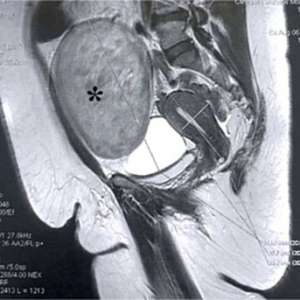

Образование в ягодичной области у пациента с множественной миеломой

Женщина, 78 лет

В анамнезе множественная миелома и AL-амилоидоз. В 2022 году проведен курс лечения бортезомибом, леналидомидом и дексаметазоном (VRD), отмечен полный ответа на лечение.

Жалобы на появление образования в ягодичной области, пациентка отмечает быстрый рост образования за 2 месяца. Она регулярно наблюдается в гематологическом отделении и амбулаторной клинике и в настоящий момент не получает поддерживающую терапию.